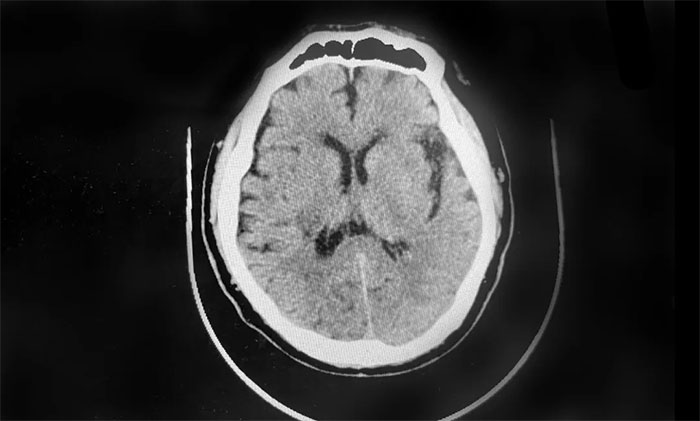

▲ 患者右侧基底节出血、蛛网膜下腔出血

患者徐老伯(化名)今年73岁。今年2月,其在打乒乓时,突感头晕伴左侧肢体活动不利,送医至就近医院。经查,患者右侧基底节出血、蛛网膜下腔出血,给予脱水降颅压等对症支持治疗。